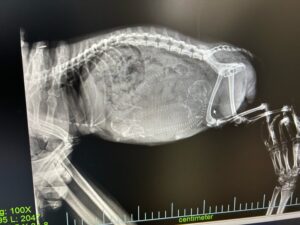

2023/12/28 ひよりちゃんカウントダウン ひよりちゃんの出産が近くなってきましたので、今日は病院へ行ってレントゲンを撮ってもらいました お腹には3ベビーが写っています あと2、3日かな・・2日かな・・と先生 また […]